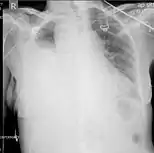

Ultrasonography may be used to detect hemothorax and other pleural effusions. This technique is of particular use in the critical care and trauma settings as it provides rapid, reliable results at the bedside.[23] Ultrasound is more sensitive than chest x-ray in detecting hemothorax.[25] Ultrasound can cause issues in people who are morbidly obese or have subcutaneous emphysema. When CT is unavailable in the current setting or the person cannot be moved to the scan, ultrasound is used.[3]

Ultrasound scan of the chest showing a left-sided hemothorax